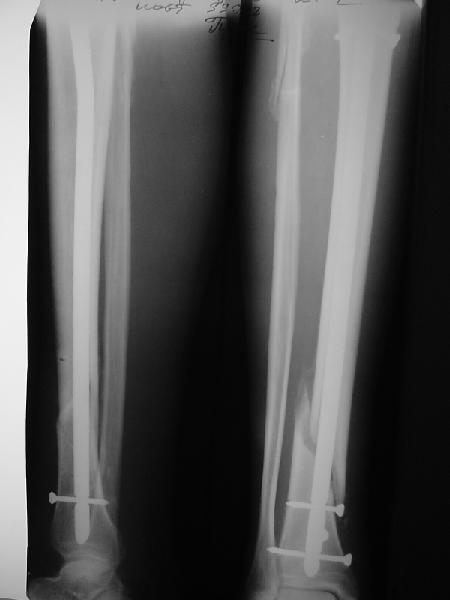

По крайней мере ходящих без дополнительной опоры через 1 месяц после операции с небольшой - при изолированной травме немало. Нестабильные по оси, кстати, не только оскольчатые, но и спиральные.

И если пациент еще не возвращается к полной нагрузке и функции, то не потому, что не разрешает врач, опасаясь несостоятельности фиксации.

Как мне показать пример? Фото стоящего на одной оперированной конечности пациента? O! Пример, подвигнувший нас на некоторое изменение технологий. Пациент этот ходил с полной нагрузкой вопреки рекомендациям. В качестве подтверждения - сломанный проксимальный статический винт к 1 мес., а к 2 мес. - все остальные. Сейчас мы перешли на более fool-proof остесинтез.

Это наглядная демонстрация возможности ранней полной нагрузки при нестабильном по оси повреждении, причем не в самых благоприятных механических условиях - при плохом сопоставлении, со слабым фиксатором.

Как я уже говорил, мы сделали выводы из этого и других подобных случаев. Очевидно, решений проблемы два - либо уменьшить нагрузку, либо увеличить прочность фиксатора. Первое решение работает не со всеми больными, так что пошли по второму пути - мы больше не используем гвозди с запирающими винтами диаметром 4 мм.